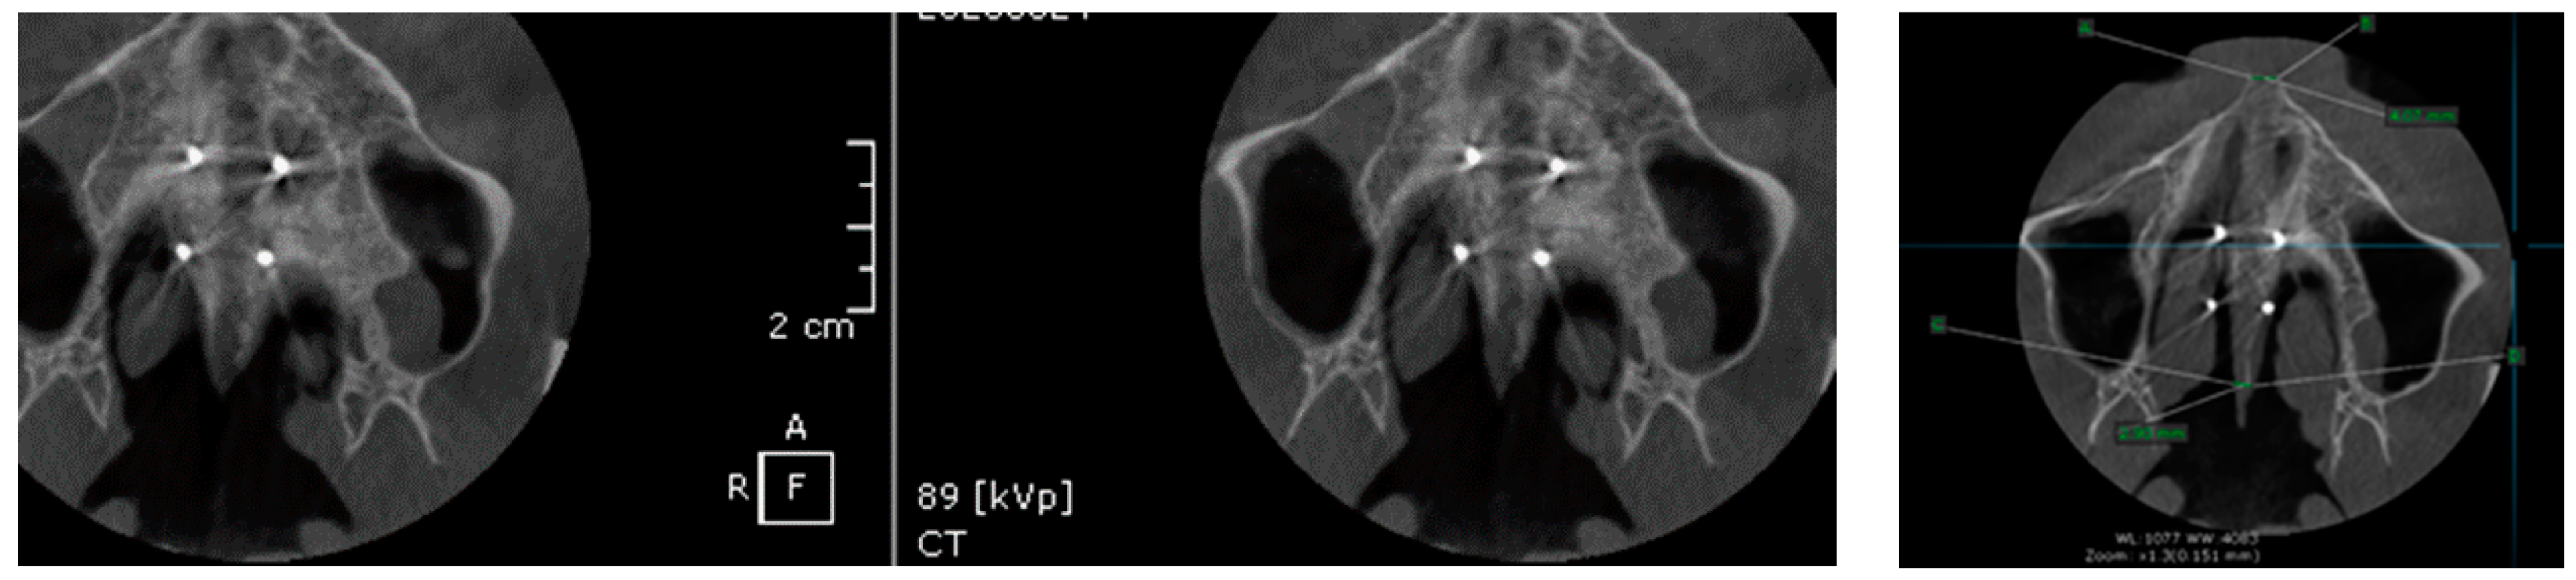

2. Materials and Method

Surgical Protocol

- Suzuki, S.S.; Braga, L.F.S.; Fujii, D.N.; Moon, W.; Suzuki, H. Corticopuncture Facilitated Microimplant-Assisted Rapid Palatal Expansion. Case Rep. Dent. 2018, 2018, 1–12. [Google Scholar] [CrossRef]